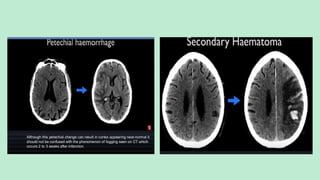

HEMORRHAGICTRANSFORMATION

Can be either Petechial and rarely Lobar.

Occur in about (20-25%) cases of Ischemic Strokes.

Occurs between (2-7 days).

Can be spontaneous or After IV tPA therapy.

HemorrhagicTransformation (about 20-25% cases) – Between 2 days to 1week.

T2* gradient echo images show the hemorrhagic transformation as petechial

or gyriform blooming foci. However in basal ganglia it can be petechial or

confluent.